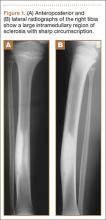

A 10-year-old boy was admitted for surgical repair of an inguinal hernia. Physical examination revealed a painless but tender anterior bowing of the right tibial diaphysis. The patient was a healthy-appearing white male with normal vital signs, gait, and posture. His parents noticed a slight protuberance of the tibia at age 2.5 years. No medical advice was asked for the bone swelling after that time. After recovery from the inguinal hernia repair 3 weeks later, the bone lesion was thoroughly examined. Radiographs showed an oblong, homogenous region of dense sclerosis in the diaphysis of the right tibia. The lesion had relatively well-defined margins and was located in the medullary cavity. Speculations were not obvious in the periphery of the lesion, which exhibited a sharp circumscription (Figures 1A, 1B). A well-defined lytic area was evident at the distal part of the lesion (Figure 1B). There was no periosteal reaction. Blood and serum chemistries were within normal limits, including serum calcium, phosphorus, and alkaline phosphatase. A conventional 3-phase bone scintigraphy (300 MBq) with technetium-99m HDP (hydroxydiphosphonate) indicated increased uptake in the area of the lesion but no other skeletal abnormality (Figure 2). Computed tomography (CT) showed that the lesion was purely intramedullary and densely blastic. The lesion originated from the medial cortex, which was thickened (Figure 3A). The lesion extended to the anterolateral cortex, which was thinned and included a lytic area. In the distal part of the lesion, the anterolateral cortex was thickened, included lytic areas, and exhibited an anterior portion of cortical destruction (Figure 3B). The fatty marrow adjacent to the region of sclerosis appeared normal. There was no evidence of extraosseous soft-tissue changes. On both T1- and T2-weighted magnetic resonance imaging (MRI), the lesion exhibited low-signal intensity. The lesion measured 10.8×2.2×1 cm. It originated from the medial cortical bone of the tibia, blended into the medullary cavity, and extended anteriorly towards and through the anterior cortex. The area of cortical destruction was clearly evident on the axial MRI. The periosteum was displaced and eroded anteriorly by focal radiating bony streaks. No enhancement was seen after the intravenous administration of gadolinium-diethylenetriamine pentaacetic acid (Gd-DTPA) as a contrast medium. There were no extraosseous soft-tissue changes. In the distal part of the lesion, sagittal and axial MRI showed a 1.2×0.8×0.7-cm well-defined ovoid focus, with characteristics of cystic degeneration that exhibited intermediate-signal intensity on T1-weighted MRI (Figure 4) and high-signal intensity on T2-weighted MRI.